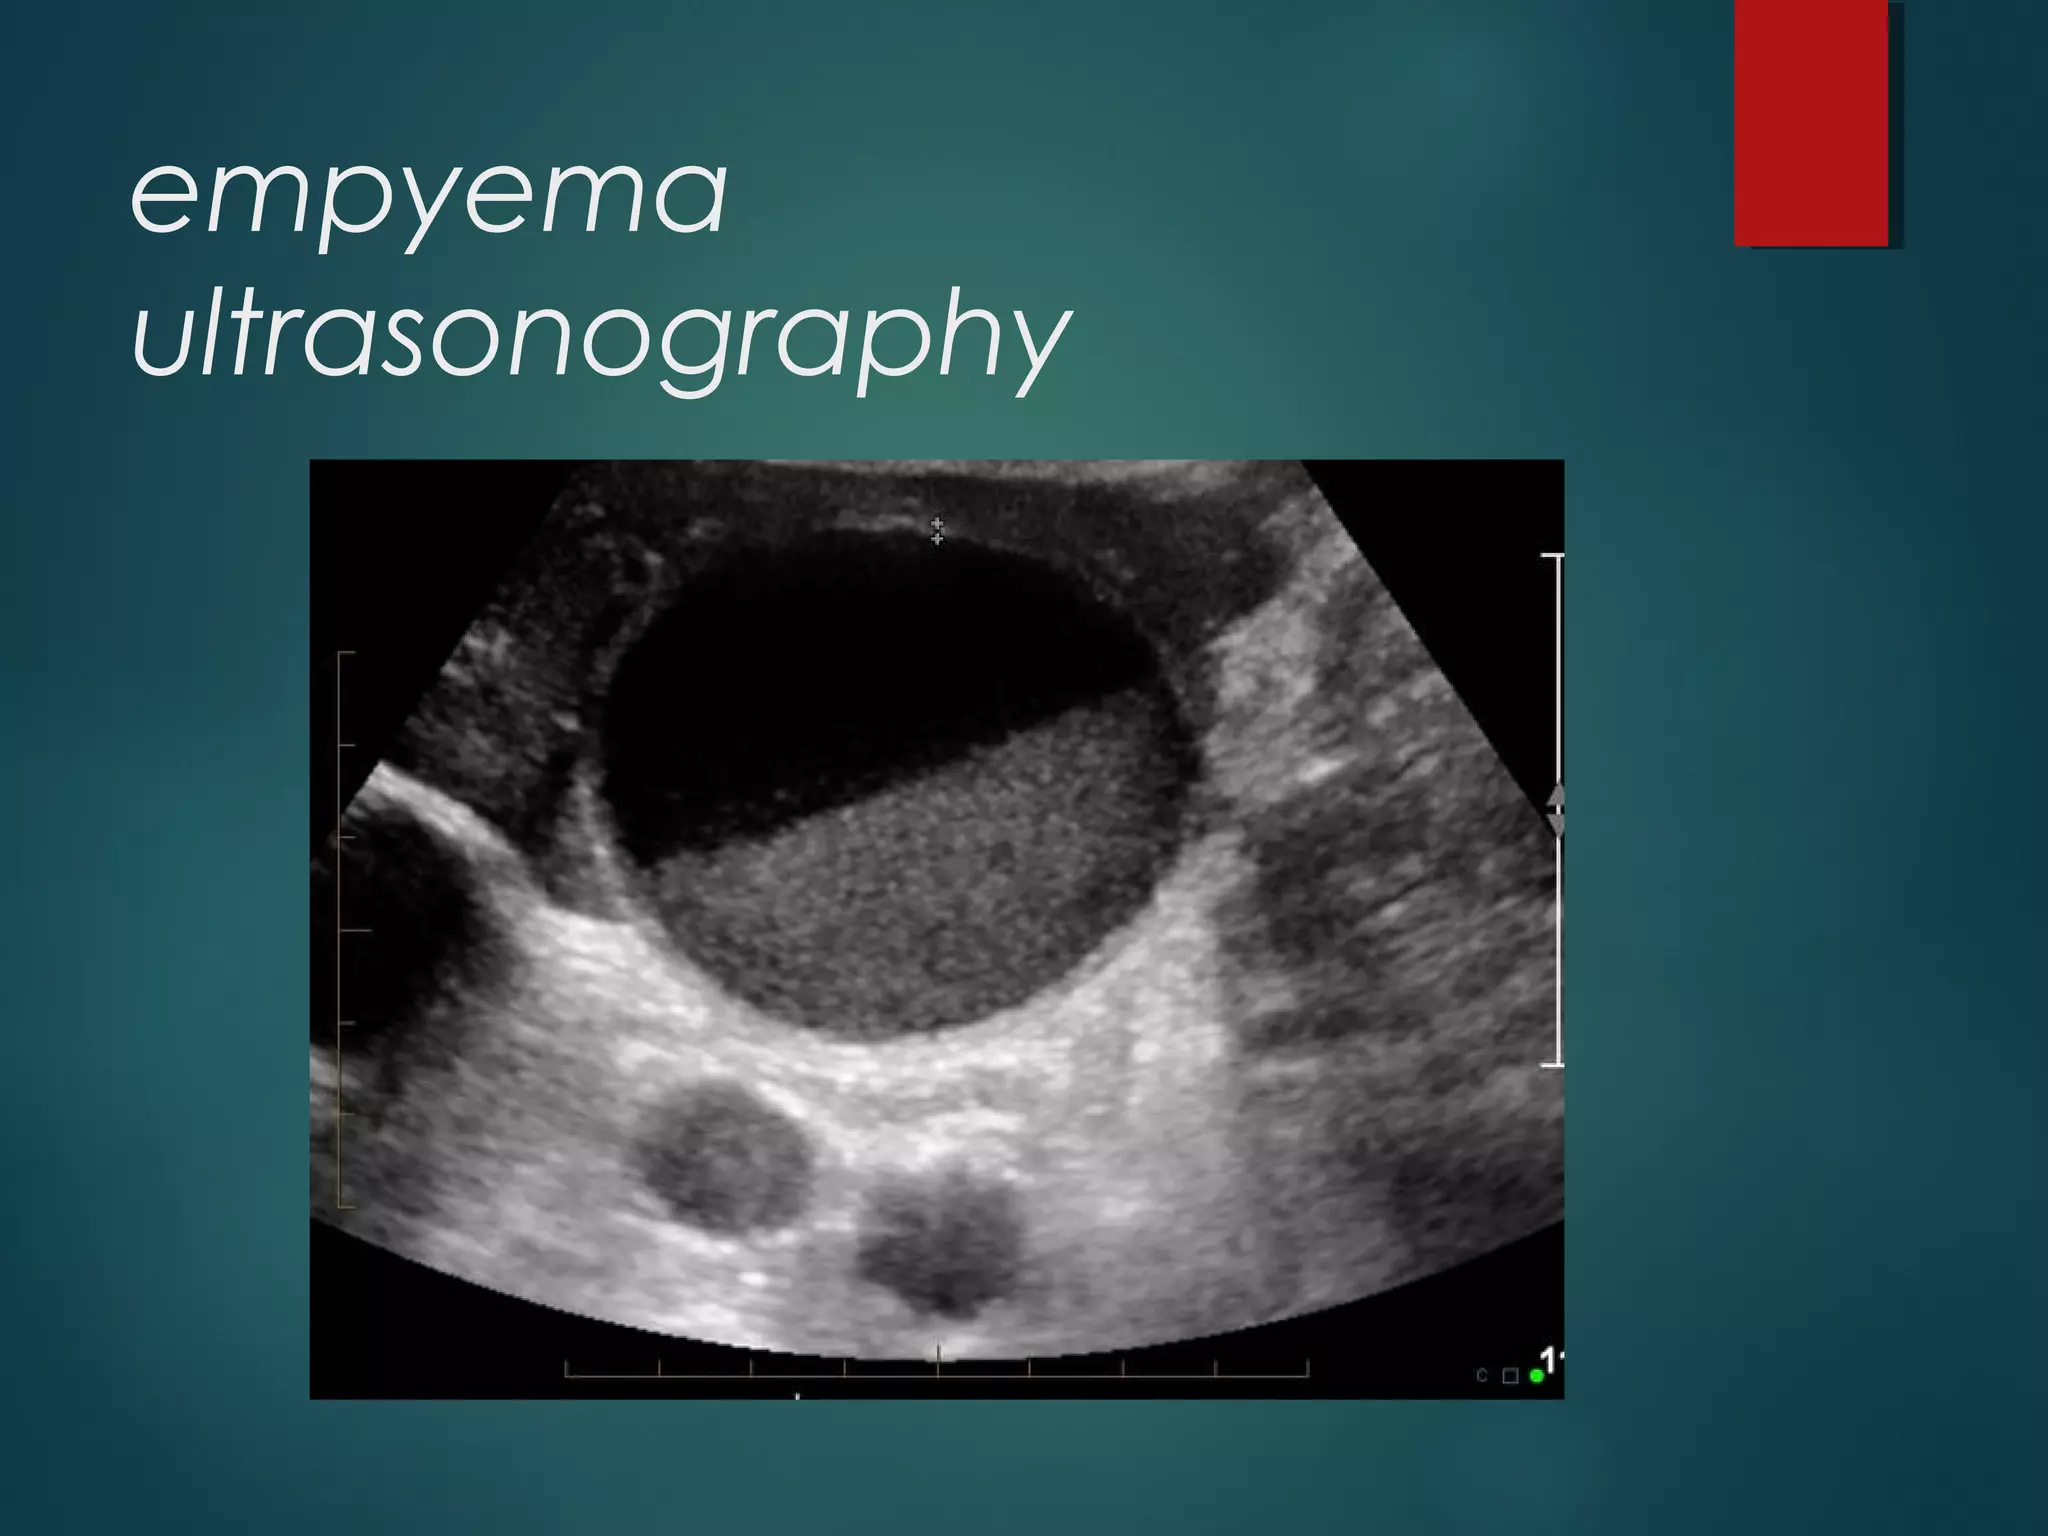

empyema

ultrasonography